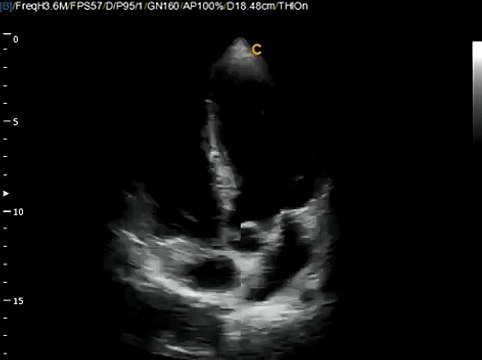

Example of volumetric probe scan with 4D Virtual HD ultrasound. Virtual HD is a breakthrough in real-time 4D technology. For more information on the low cost color doppler ultrasound Chison Q5, and Chison Q9 visit: keebomed.com/collections/color-doppler-ultrasounds